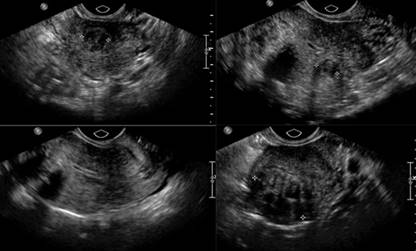

Paciente mujer de 38 años con sangrado transvaginal abundante, dolor en hipogastrio, y antecedentes de trastornos menstruales. Se desconoce la fecha de su última menstruación.

1. ¿Qué tipo de estudio se observa en las imágenes presentadas?

Ultrasonido transvaginal.

2. ¿Según las imágenes, cuál es su impresión diagnóstica?